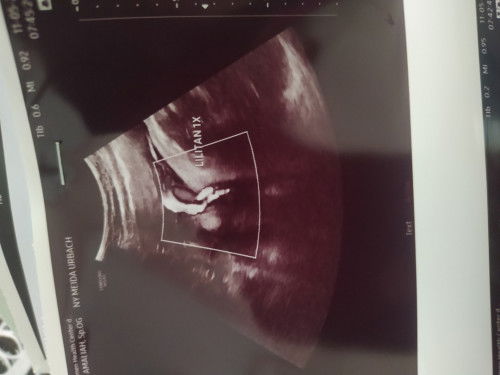

Flek coklat usia 10 minggu 4 hari

Bund, mohon pencerahannya tadi saya sempat nyuci baju dari mesin cuci terus di keluarin lanjut disikat2 lalu di bilas manual ngeringin juga... abis itu pipis kaya ada coklat2 keluar... terus gak tak pikir kirain salah liat... abis itu rapat 2 jam motoran 20 menit PP 40 menitan... pulang2 ternyata ngeflek ky gitu bund... apakah hanya kecapean atau kenapa ya bund? perut gak kerasa apa2... kayak baik2 aja... tp ttp kaya kepikiran juga.. mohon pencerahan bunnn... #seriusnanya #bantusharing #ingintahu #firstmom #pleasehelp #firstbaby